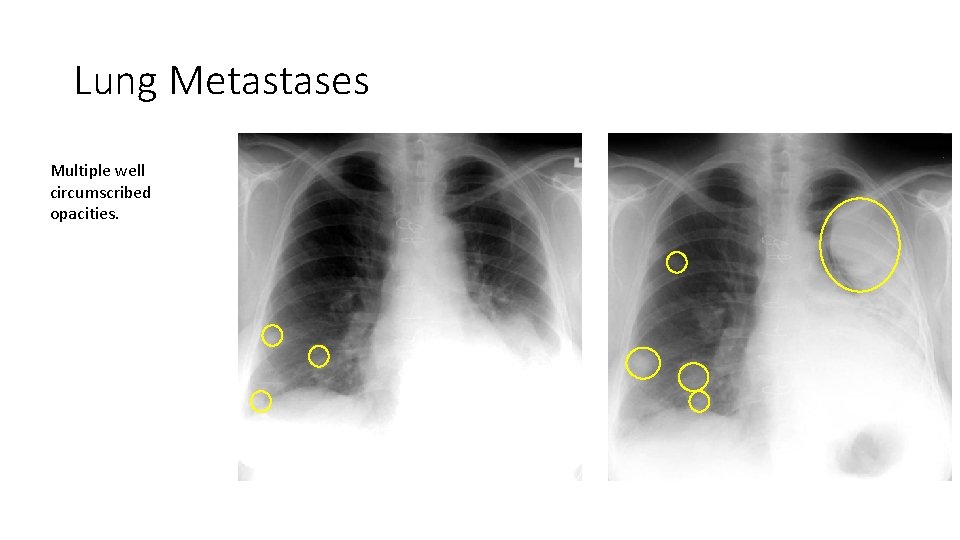

Lung Metastases Multiple well circumscribed opacities.